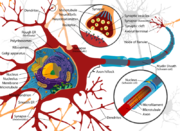

| 30. 5. 2010, 10:31 | Complete neuron cell diagram.png (soubor) |  | 321 kB | Webmaster | 1 | |